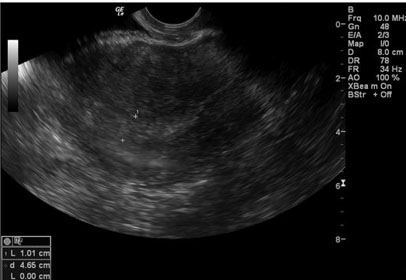

Computed tomography abdomen and pelvis demonstrated extensive subcutaneous emphysema along the anterior abdominal wall with mild surrounding fatty stranding (Figure 1). There was no evidence of fluid collection or abscess. The patient was subsequently receiving serial abdominal examinations, vitals remained stable, and repeat complete blood count demonstrated a stable hemoglobin, from 13.4 to 12.9 g/dL, and appropriate postoperative white blood cell count. The patient remained afebrile and symptoms began to resolve. She was discharged on postoperative day 2 with counseling for return precautions of signs or symptoms of infection or bleeding.

Figure 1: CT abdomen/pelvis findings demonstrating subcutaneous emphysema (arrow).